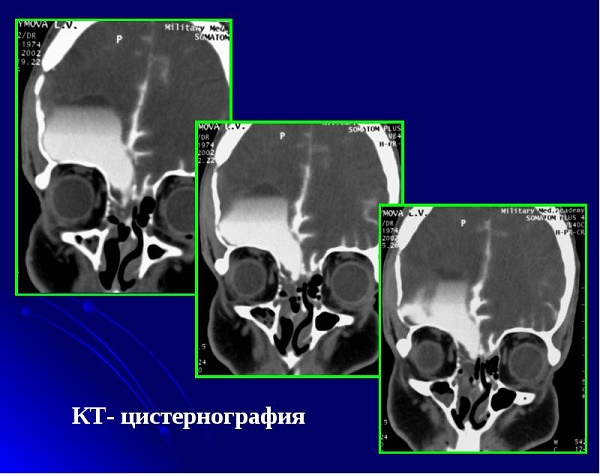

- Томографія (комп'ютерна і магнітно-резонансна). За допомогою неї можна дізнатися причину патологічного процесу і побачити вогнище скупчення ліквору;

- Цистернографія. Її застосовують для визначення різновиду водянки.

Для з'ясування причини скупчення спинномозкової рідини, лікуючий лікар також може використовувати рентген з контрастною речовиною і нейропсихологічне обстеження. Якщо діагноз підтвердиться, то буде складена схема лікування в залежності від типу хвороби.